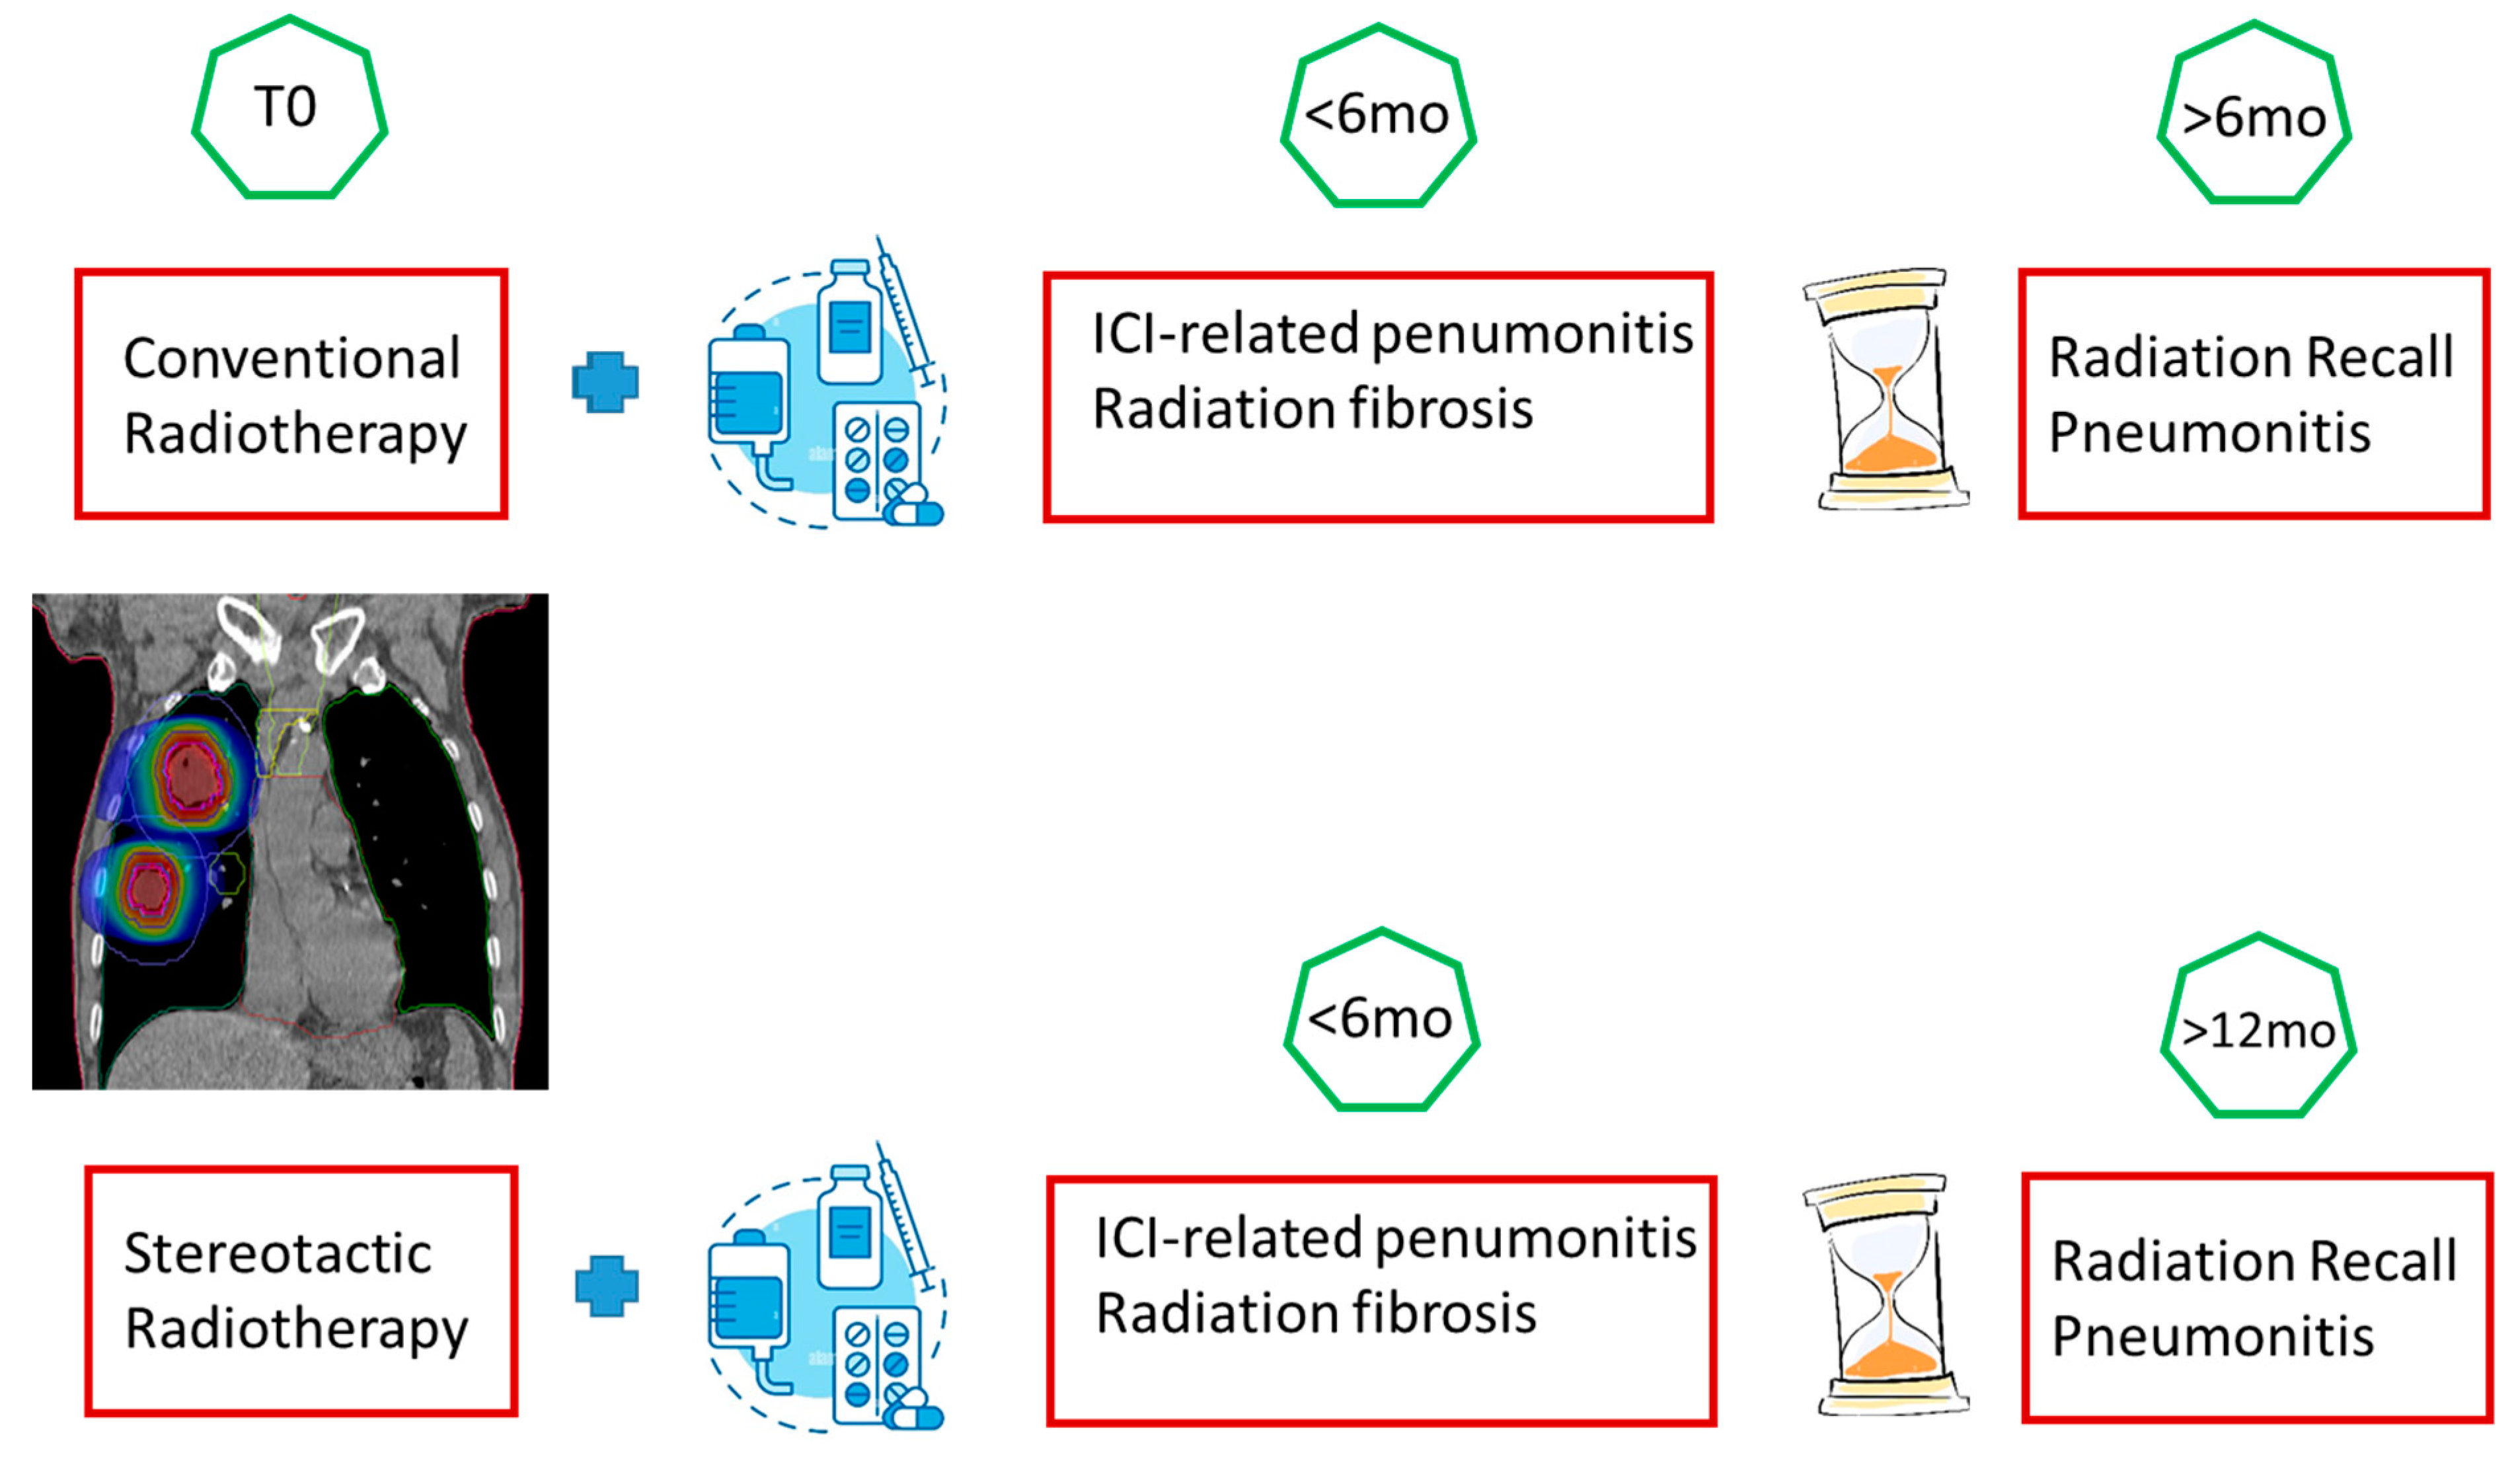

3.1. Radiological and Clinical Setting

Radiation Recall Pneumonia

3.3. Radiation Pneumonia